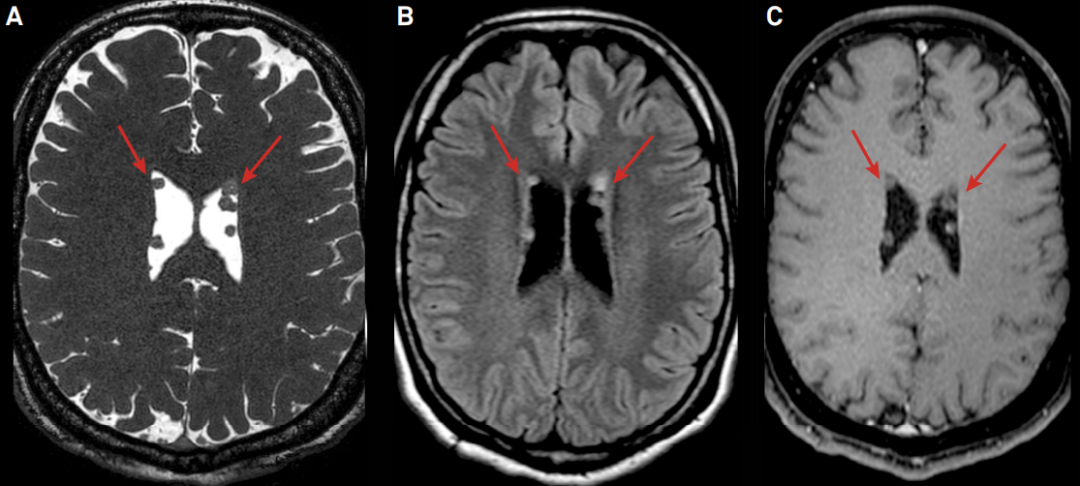

右侧侧脑室壁见结节样异常信号,T2WI 周围低信号,中心高信号,T1WI 呈周围等信号,中心低信号,FLAIR 呈高信号,DWI 及 ADC 图呈等信号。

MR 表现:表现为室管膜下单个或多个结节样信号,体积往往比较小,即使多个大小也相当。T1WI 表现为结节样等信号,中心呈低信号,T2WI 表现为等信号,中心高信号,FLAIR 呈稍高信号,增强扫描不会出现强化。